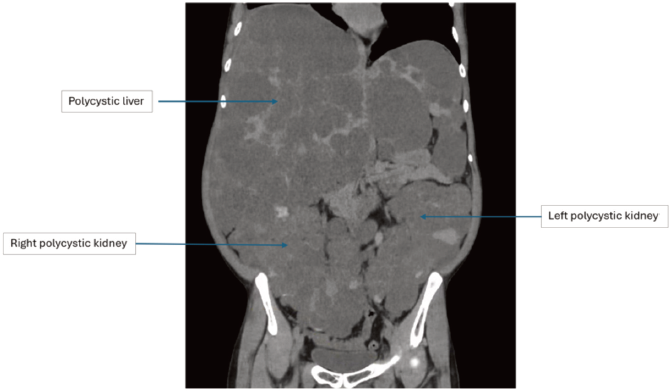

The recipient was a 48-year-old male patient with ADPKD and significant liver involvement. The Chronic Kidney Disease Epidemiology estimated glomerular filtration rate (eGFR) for this patient was 20 mL/min/1.73 m2. He had developed massive hepa-tomegaly and malnutrition. His other comorbidities included refractory hypertension, treated latent tuberculosis, Crohn disease, and pancreatic intraductal papillary mucinous neoplasm. Following multidis-ciplinary assessment, he was listed for SLKT.6 A right-side nephrectomy was necessary due to the large size of the kidney (Figure 1).